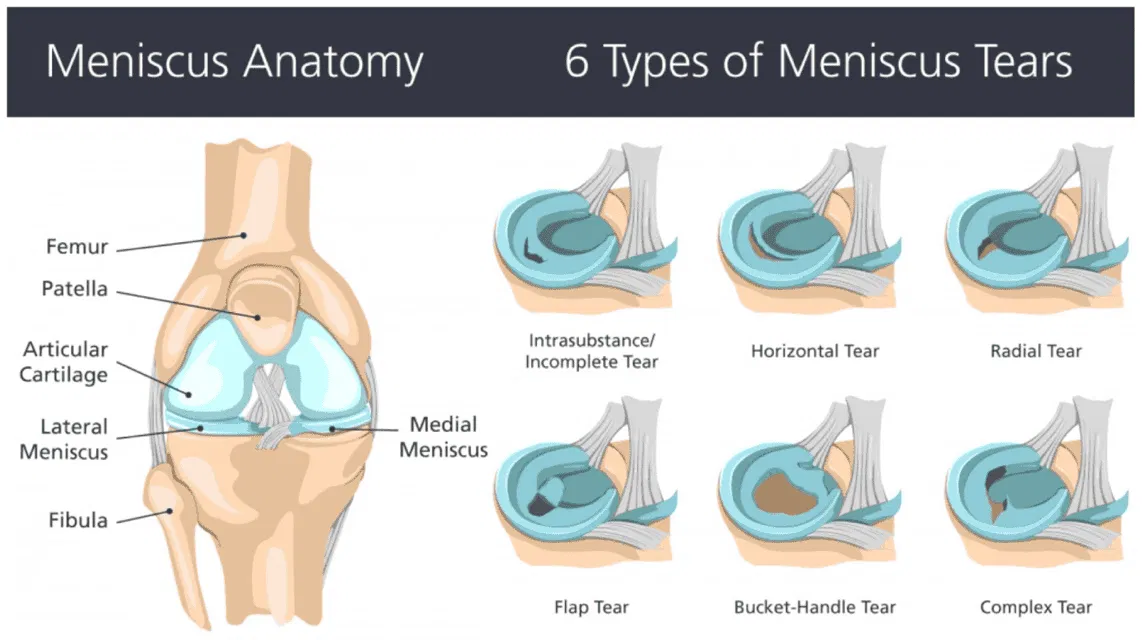

Where further information is required, imaging may be recommended. We are able to offer point-of-care diagnostic ultrasound scans in clinic where appropriate, however ultrasound is often not the imaging modality of choice concerning the knee due to its inability to identify deep structures of the knee such as the medial meniscus, lateral meniscus and cruciate ligaments (anterior cruciate ligament (ACL) and posterior cruciate ligament (PCL))

An MRI scan is the gold standard for visualising soft tissue structures including the meniscus, and can confirm the location, type, and severity of a tear. A weight-bearing x-ray may also be helpful to rule out bony involvement or assess for arthritic changes.

Not necessarily. Most running knee injuries can be confidently diagnosed through clinical assessment alone. Imaging may be recommended if there are features suggesting structural pathology such as a ligament or cartilage injury, or if symptoms are not responding as expected to treatment.

At London Sports Physiotherapy we offer advanced point-of-care diagnostic ultrasound scans when indicated. These can be helpful for visualising the superficial structures but is not the recommended imaging modality of choice as it is unable to visualise deeper structures of the knee such as the meniscus or cruciate ligaments.